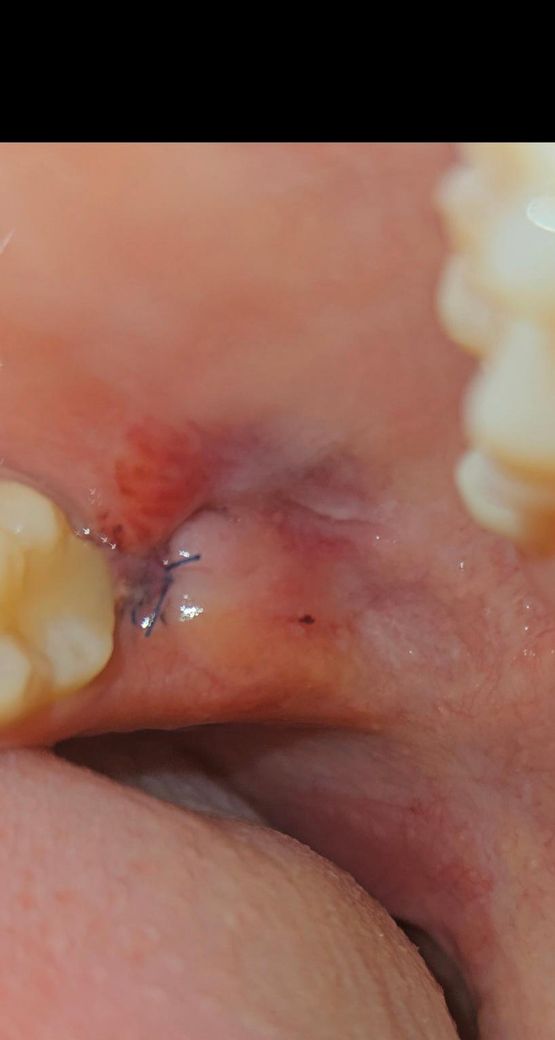

사랑니 1일찬데 잘 된거 맞을까요??

어제 저녁에 뽑았는데

혈병이 거의 없능거 같아서..

잘 아물어가고 있는거 맞을까요?

피는 거의 안납니다. 괜찮을까요?ㅠㅠㅠㅠㅠ

사진상으로 발치한곳 잇몸이 잘 아물고 잇는거 같습니다. 크게 걱정은 안하셔도 될것같습니다.

피는 거의 안납니다. 괜찮을까요? -> 네 사진상 별 문제 없어보입니다.